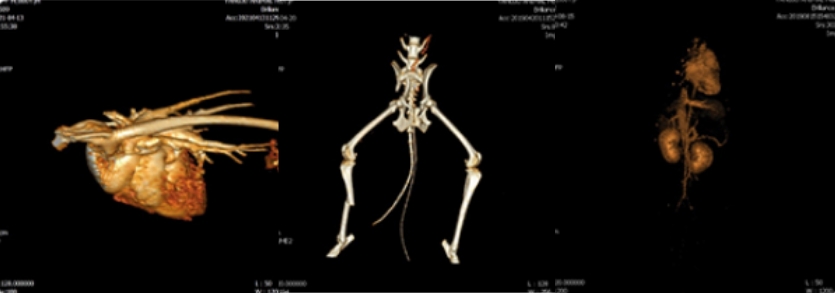

CT/3D-CT 검사

CT 검사는 방사선을 이용하여 신체 구조물의

단면을 영상화 하는 검사 장비로

눈으로

보기 힘든 부분을 정밀하게 볼 수 있으며,

혈관 조영 및 3D 재구성을 통해 수술과 같은

처치를 보다 안전하고 완벽하게 진행하는데

도움을 줄 수 있습니다.

3D-CT 검사

이럴 때 필요해요.

선천적인 혈관 이상이나 단순한 골절이 아닌

복합적인 골절이 발생한 경우 3D 재구성을 통해

한눈에 병변과 이상을 확인할 수 있습니다.